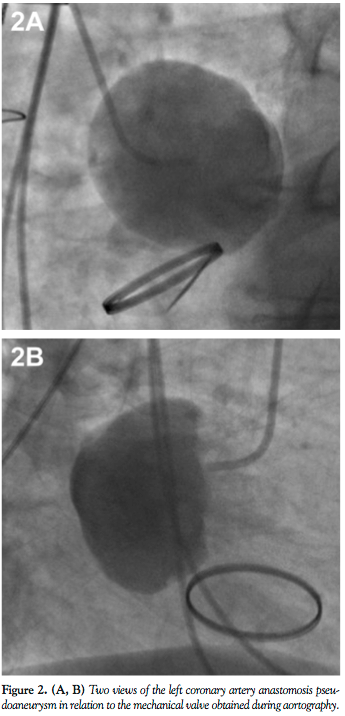

A 69-year-old male underwent a classic Bentall procedure for ascending aortic aneurysm at an outside institution. The patient had done reasonably well until 7 years later when he was admitted to an outside hospital with 2 weeks of fatigue and an episode of exertional dyspnea. Chest computed tomography angiogram revealed a large aortic root pseudoaneurysm at the left main coronary artery with pericardial hematoma (Figure 1). The patient was transferred to our institution for further workup. Aortography performed at our institution

confirmed the findings (Figures 2 and 3; Videos 1-3 available at www.invasivecardiology.com). The patient underwent a successful operative repair of the pseudoaneurysm and was discharged home 8 days later.